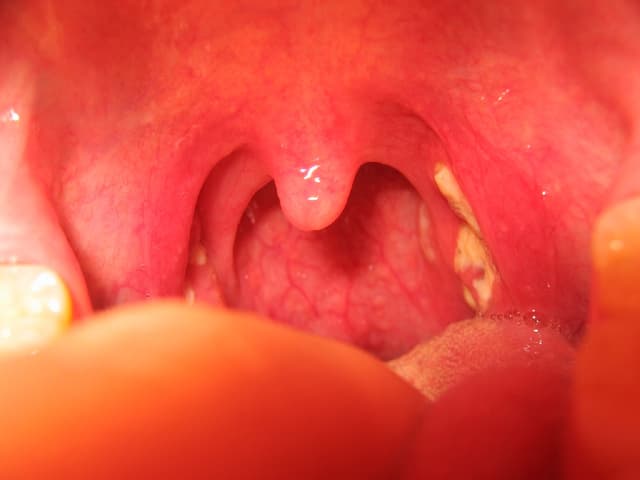

Amidan là 2 mô đệm hình bầu dục nằm ở phía sau cổ họng. Viêm Amidan gồm 2 loại: Cấp tính và mạn tính. Mỗi loại viêm Amidan lại có một cách điều trị khác nhau. Ở bài này, hãy cùng tìm hiểu về cách chữa viêm Amidan nhé. 1. Viêm Amidan là tình trạng […]

Viêm amidan mủ (hoặc viêm amidan hốc mủ) là tình trạng tổn thương bị viêm nhiễm cấp tính hoặc mạn tính của tuyến amidan do vi khuẩn gây nên. Nếu không được kịp thời phát hiện và chữa trị đúng cách, bệnh có thể dẫn đến nhiều biến chứng nguy hiểm. Vậy nguyên nhân và […]

Viêm amidan hốc mủ là một trong những yếu tố gia tăng nguy cơ ung thư vòm họng nếu không được điều trị kịp thời. Vậy nguyên nhân gây bệnh và mức độ ảnh hưởng tới sức khỏe của bệnh như thế nào? 1. Viêm amidan hốc mủ là gì? Viêm amidan hốc mủ là […]

Viêm amidan là loại bệnh tai-mũi-họng thường gặp ở trẻ em. Người trưởng thành cũng có thể mắc nhưng ít hơn. Đặc biệt bệnh thường tái phát nhiều lần, dễ biến chứng, gây ảnh hưởng đến sức khỏe và thời gian sinh hoạt, học tập của trẻ. Vậy có nên cắt amidan không? Và khi […]